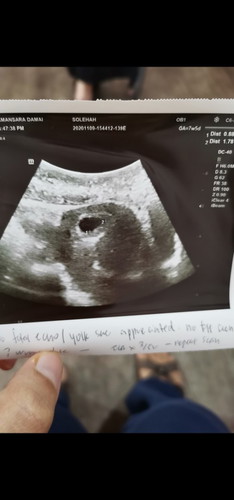

Kalau ikut tarikh period, patut minggu ni da 8w..tp scan mcm 5-6w..normal ke? Mcm jauh sgt je gapπ

Normal. Doktor kira bdsrkn ukur pnjg lilit kantung yg tercipta.. Congrats puan Stay safe & healty #TAPSupermoms #TAPactiveusers